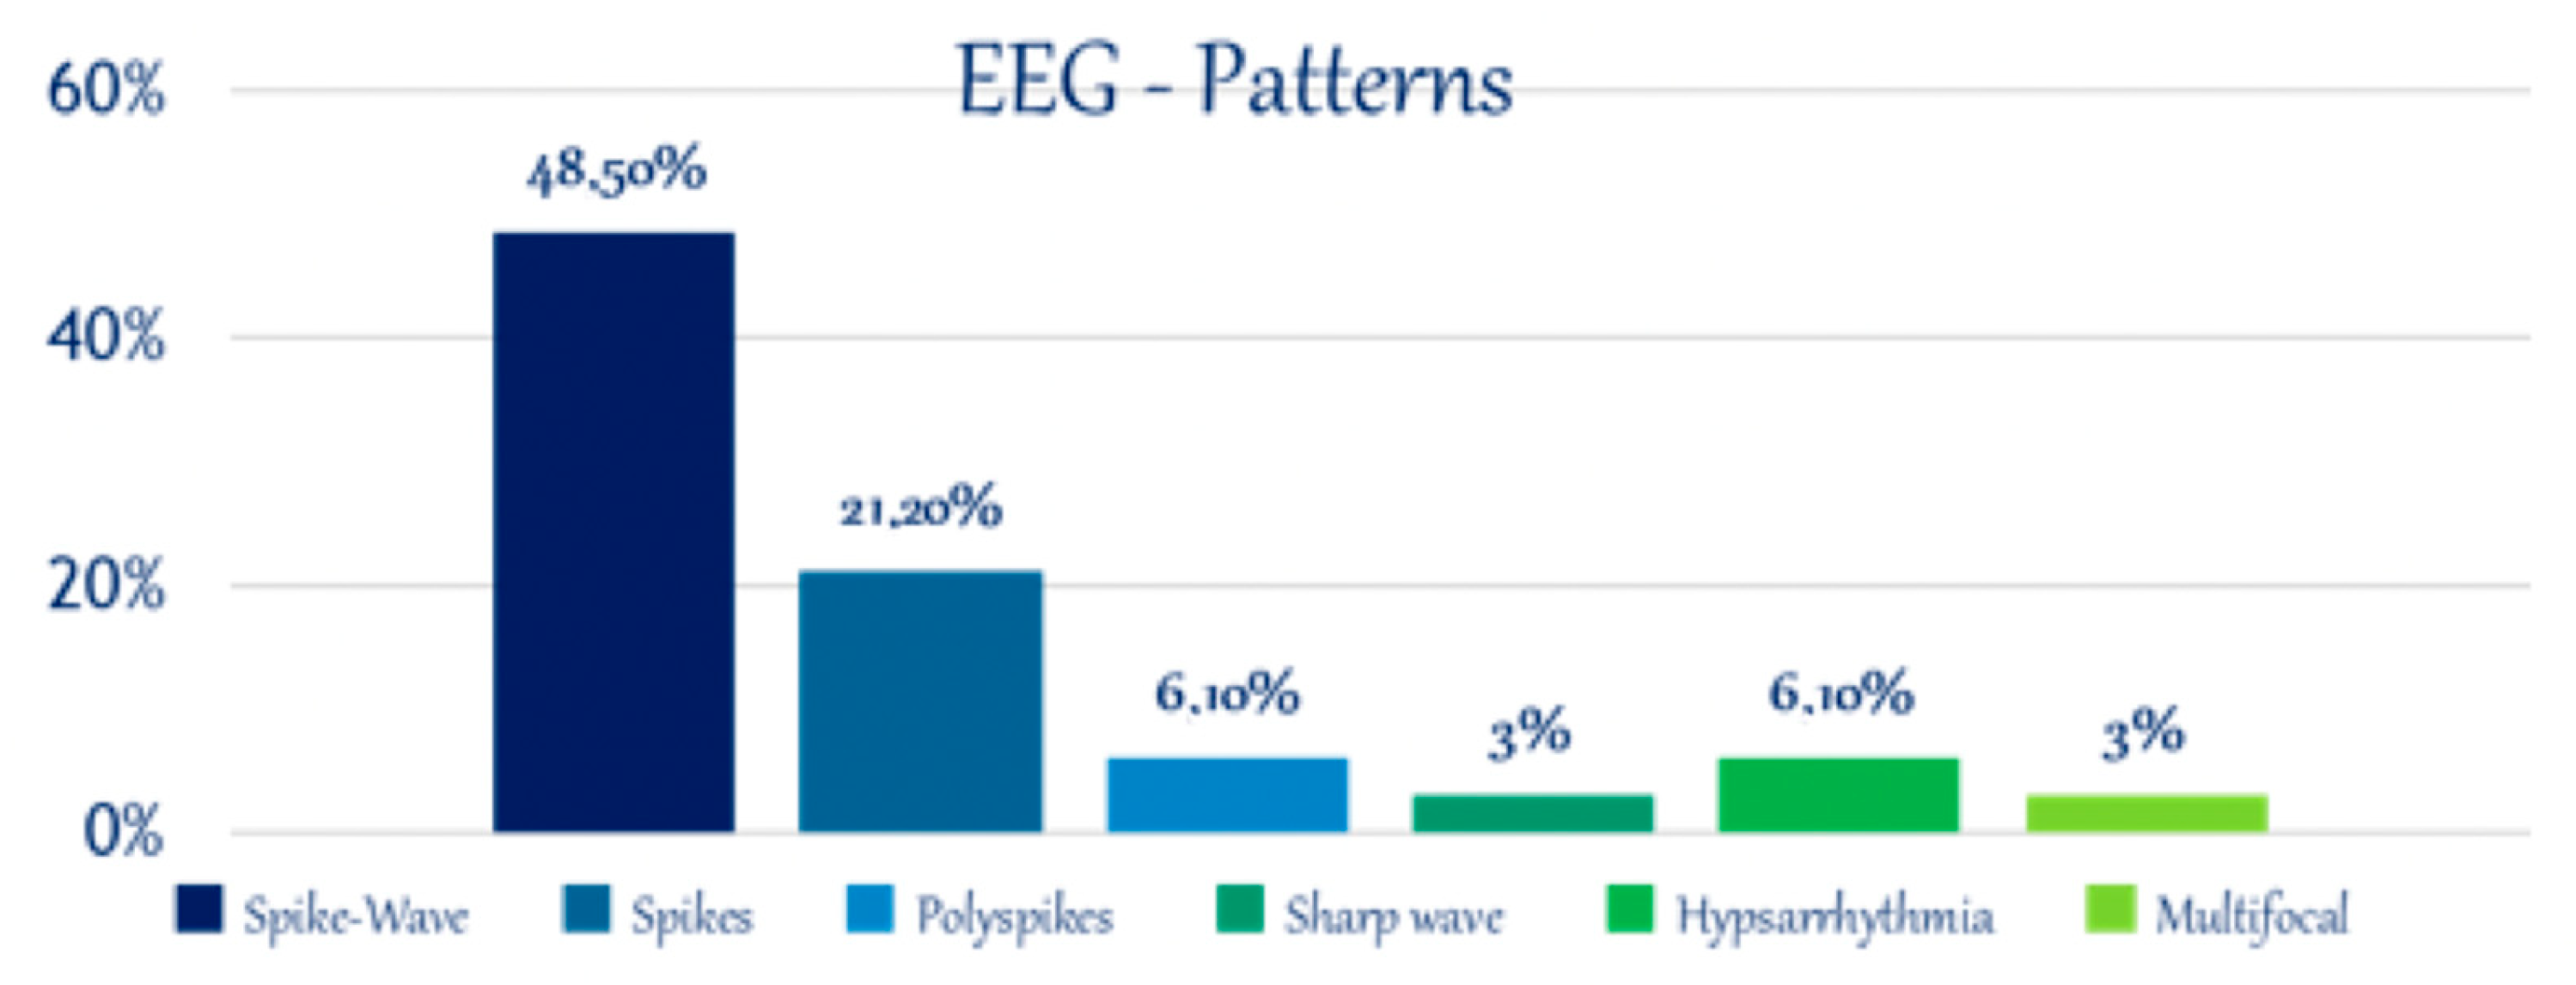

3.3. Electroencephalography